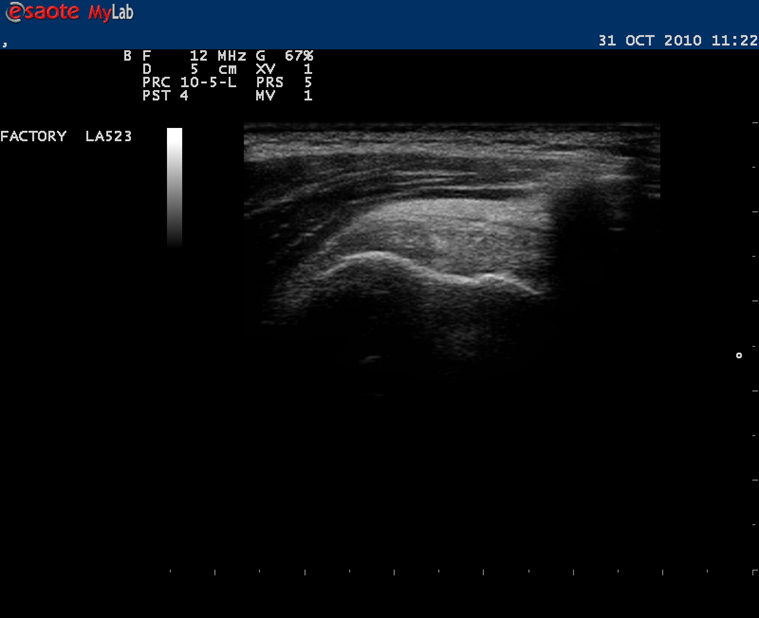

Obraz USG przestrzeni podbarkowej podczas techniki sonofeedback dla centrowania głowy k. ramiennej w zespołach cieśni podbarkowej